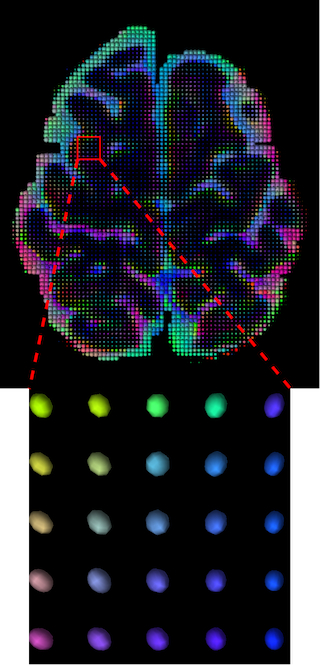

The visualization of inpainted results (showing the whole diffusion tensor for each voxel) generated from different models are demonstrated in Figure 3, where the tensor is represented in RGB coding that colours red, green and blue represent diffusion in the x, y, and z axes respectively. One typical example of reconstruction in the disrupted ROIs has been zoomed for visualization. Compared to the ground truth, TW-BAG is able to generate more distinct orientations following the original distribution and intensity across sagittal, coronal and axial views, which could demonstrate water diffusivity (denoted by eigenvalues of tensor model) more accurately. As indicated in Figure 4, the boundaries and textures of the FA map for TW-BAG are less blurry than the other competing models, validating the effectiveness of TW-BAG from a neuroscience perspective.